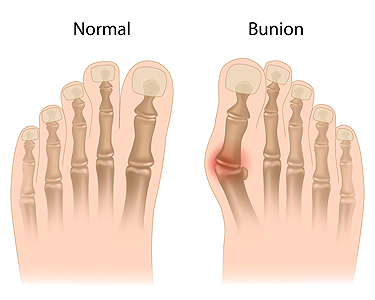

Men and Bunions

Men and BunionsA bunion is identified as a bony protrusion that gradually forms on the side of the big toe. It affects women more than men, and this may be a result of the type of shoes that are frequently worn. High heels fall into this category, because they have...